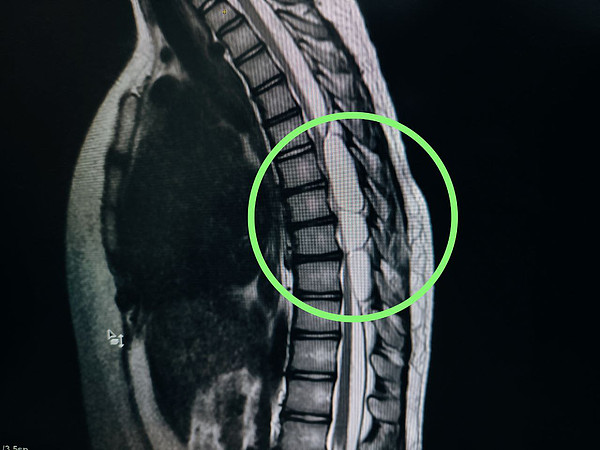

photo_2025-06-17_15-49-34photo_2025-06-17_15-49-35 (2)photo_2025-06-17_15-49-35 (3)photo_2025-06-17_15-49-35> > >

photo_2025-06-17_15-49-35 (2).